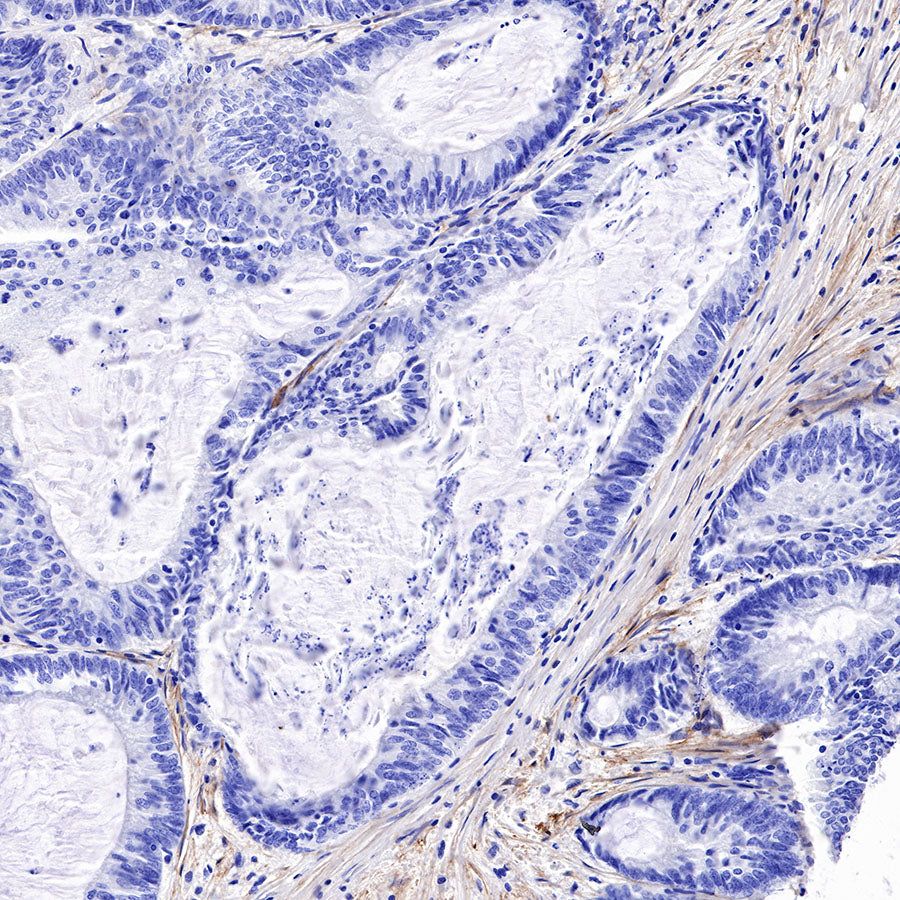

Immunohistochemistry

IHC shows positive staining in paraffin-embedded human colon cancer. Anti-FAP antibody was used at 1/500 dilution, followed by a HRP Polymer for Mouse & Rabbit IgG (ready to use). Counterstained with hematoxylin. Heat mediated antigen retrieval with Tris/EDTA buffer pH9.0 was performed before commencing with IHC staining protocol.